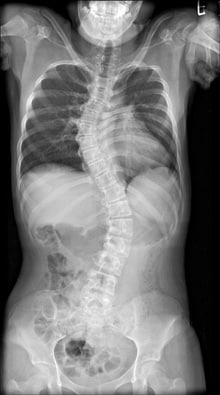

The combination of SONIALVISION G4's extra-long imaging chain slide coverage and 17” large FPD realizes even wider imaging coverage (Max.145cm × 42cm) than that of CR's image stitching.

Wide imaging range to cover from cervical spine to lumbar spine

(Courtesy of Tottori University Hospital, Japan)